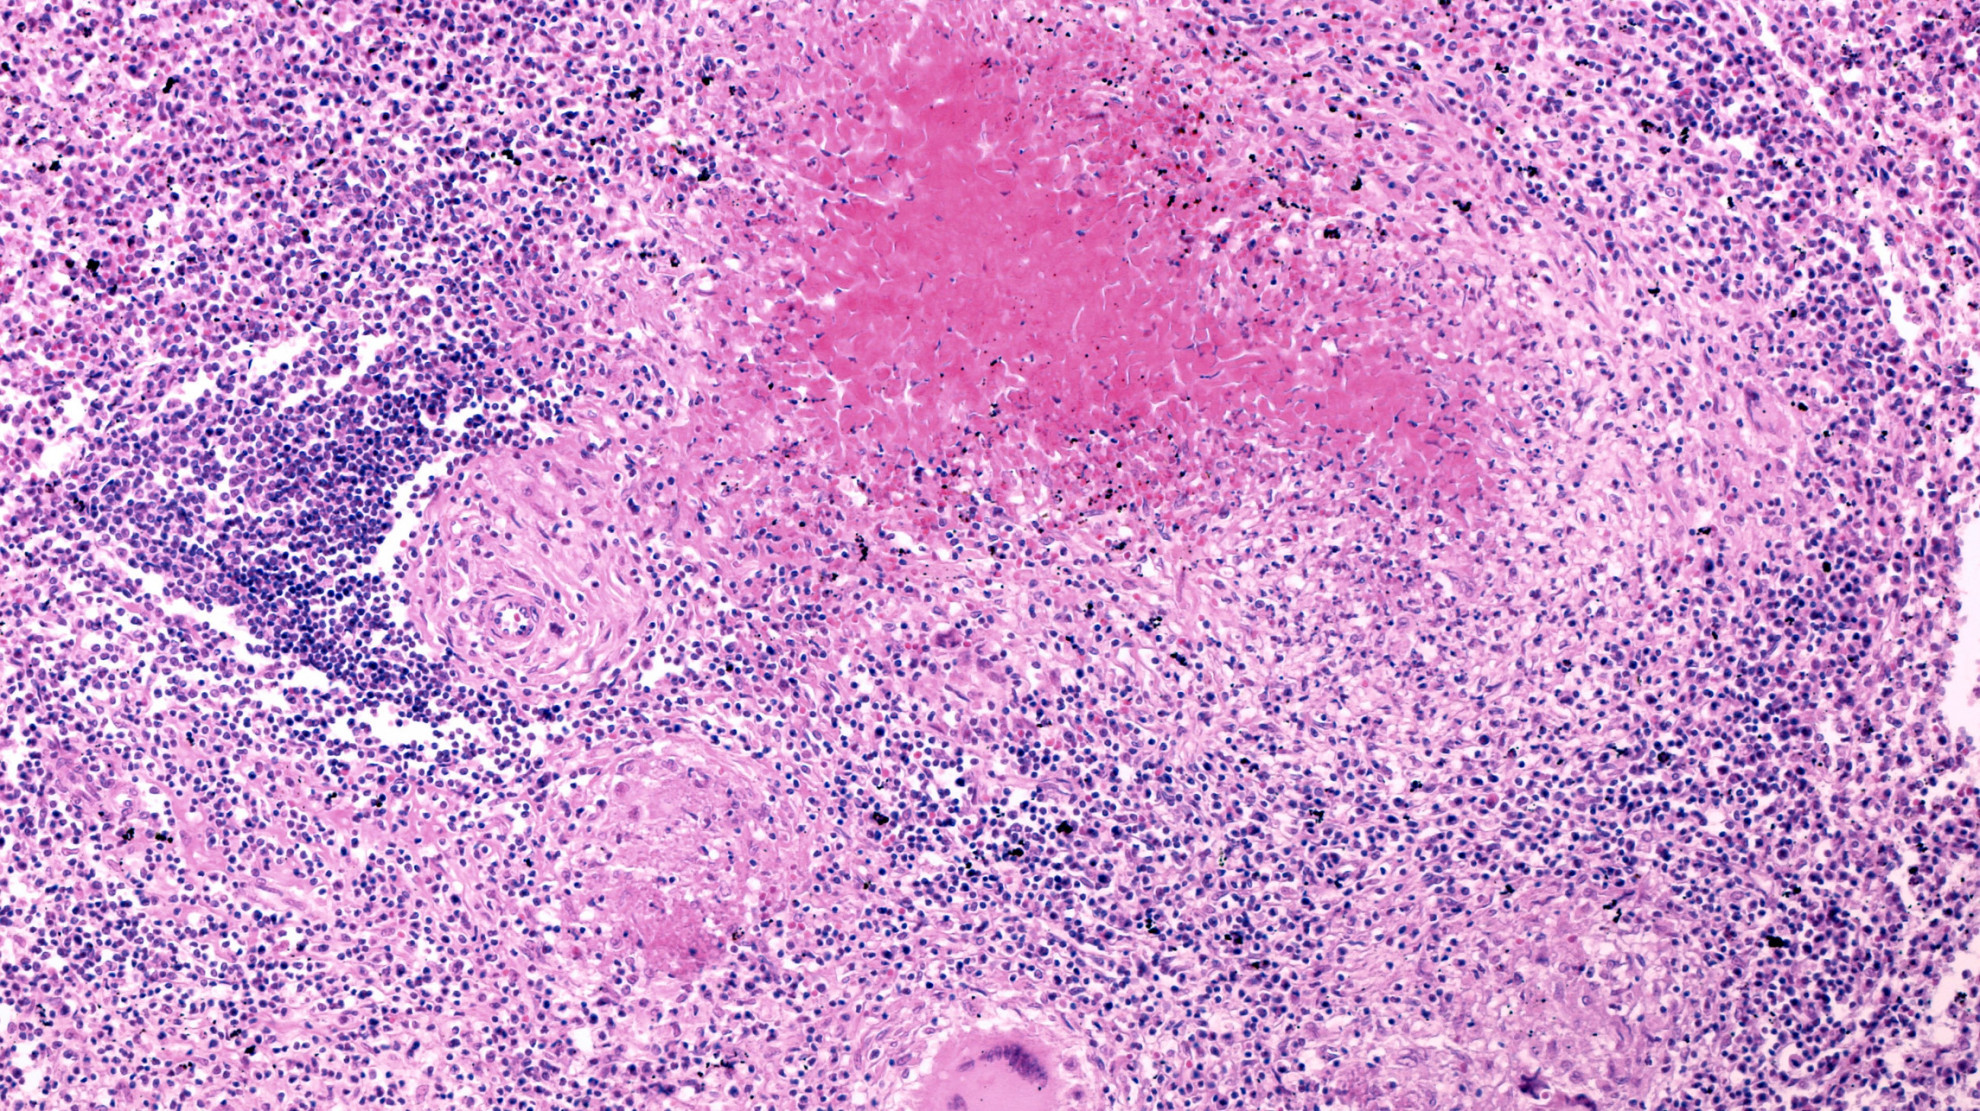

Согласно отчету, в России в 2024 году зарегистрировано самое большое число случаев туберкулеза — 49 тыс. или 34 случая на 100 тыс. населения. При этом по заболеваемости на 100 тыс. населения на первом месте в Европе находится Украина (86 случаев). За ней следуют Таджикистан (75 случаев), Азербайджан и Молдавия (по 64 случая). В России выявлено 14 236 случаев легочной формы туберкулеза с множественной лекарственной устойчивостью (у 45,4% пациентов).

Распространенность заболевания с множественной лекарственной устойчивостью в Европе значительно превышает общемировой показатель (23% в сравнении с 3,2%). Около половины (51%) ранее леченных случаев заболевания устойчивы к рифампицину. В мире этот показатель составляет только 16%.